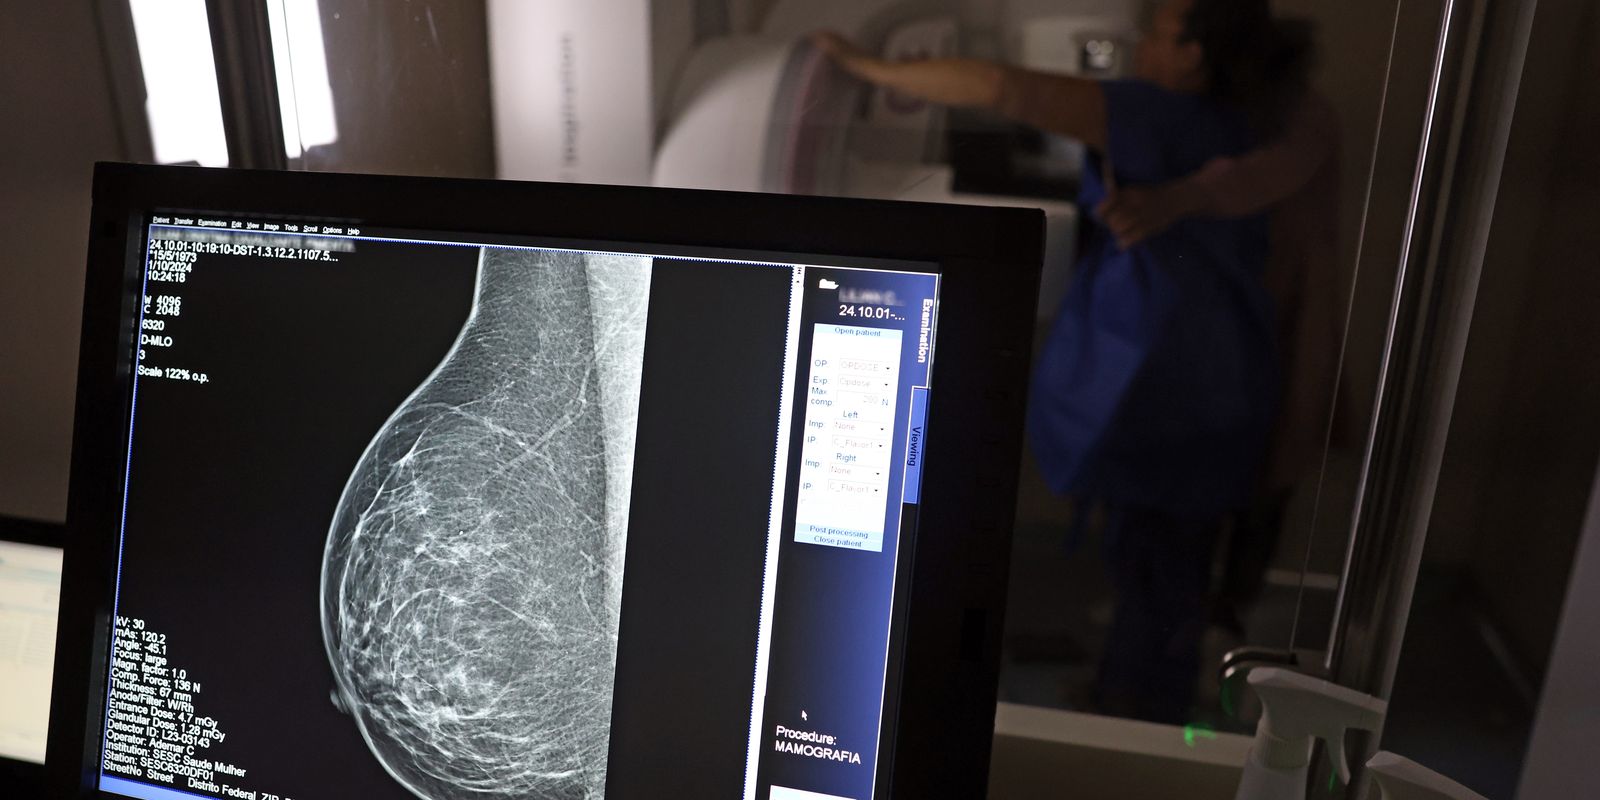

Cerca de 77 mil mulheres aguardam mamografia pelo SUS

Em junho deste ano, 77.243 brasileiras aguardavam por uma mamografia no Sistema Único de Saúde (SUS). Santa Catarina é o estado com mais mulheres na fila de espera, cerca de 17 mil. Em seguida, aparecem São Paulo (15 mil) e Rio de Janeiro (12,5 mil). Juntos, os três estados somam 56% do total de pacientes à espera do principal exame para detecção do câncer de mama. Os dados foram divulgados nesta quinta-feira (31) pelo Colégio Brasileiro de Radiologia e Diagnóstico por Imagem (CBR).

Segundo a entidade, em alguns locais do país, o tempo de espera por uma mamografia na rede pública pode chegar a 80 dias. O exame, quando realizado em tempo hábil, permite a detecção precoce de alterações mamárias, aumentando as chances de tratamento bem-sucedido e reduzindo a necessidade de intervenções invasivas e onerosas. “Os números revelam parte da sobrecarga no SUS e devem ser levados em conta, especialmente pelos recém-eleitos nas eleições municipais, na formulação e manutenção de políticas de saúde pública”, avaliou o CBR.